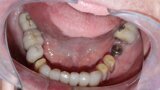

Figure 7 Mandibular occlusal view before treatment